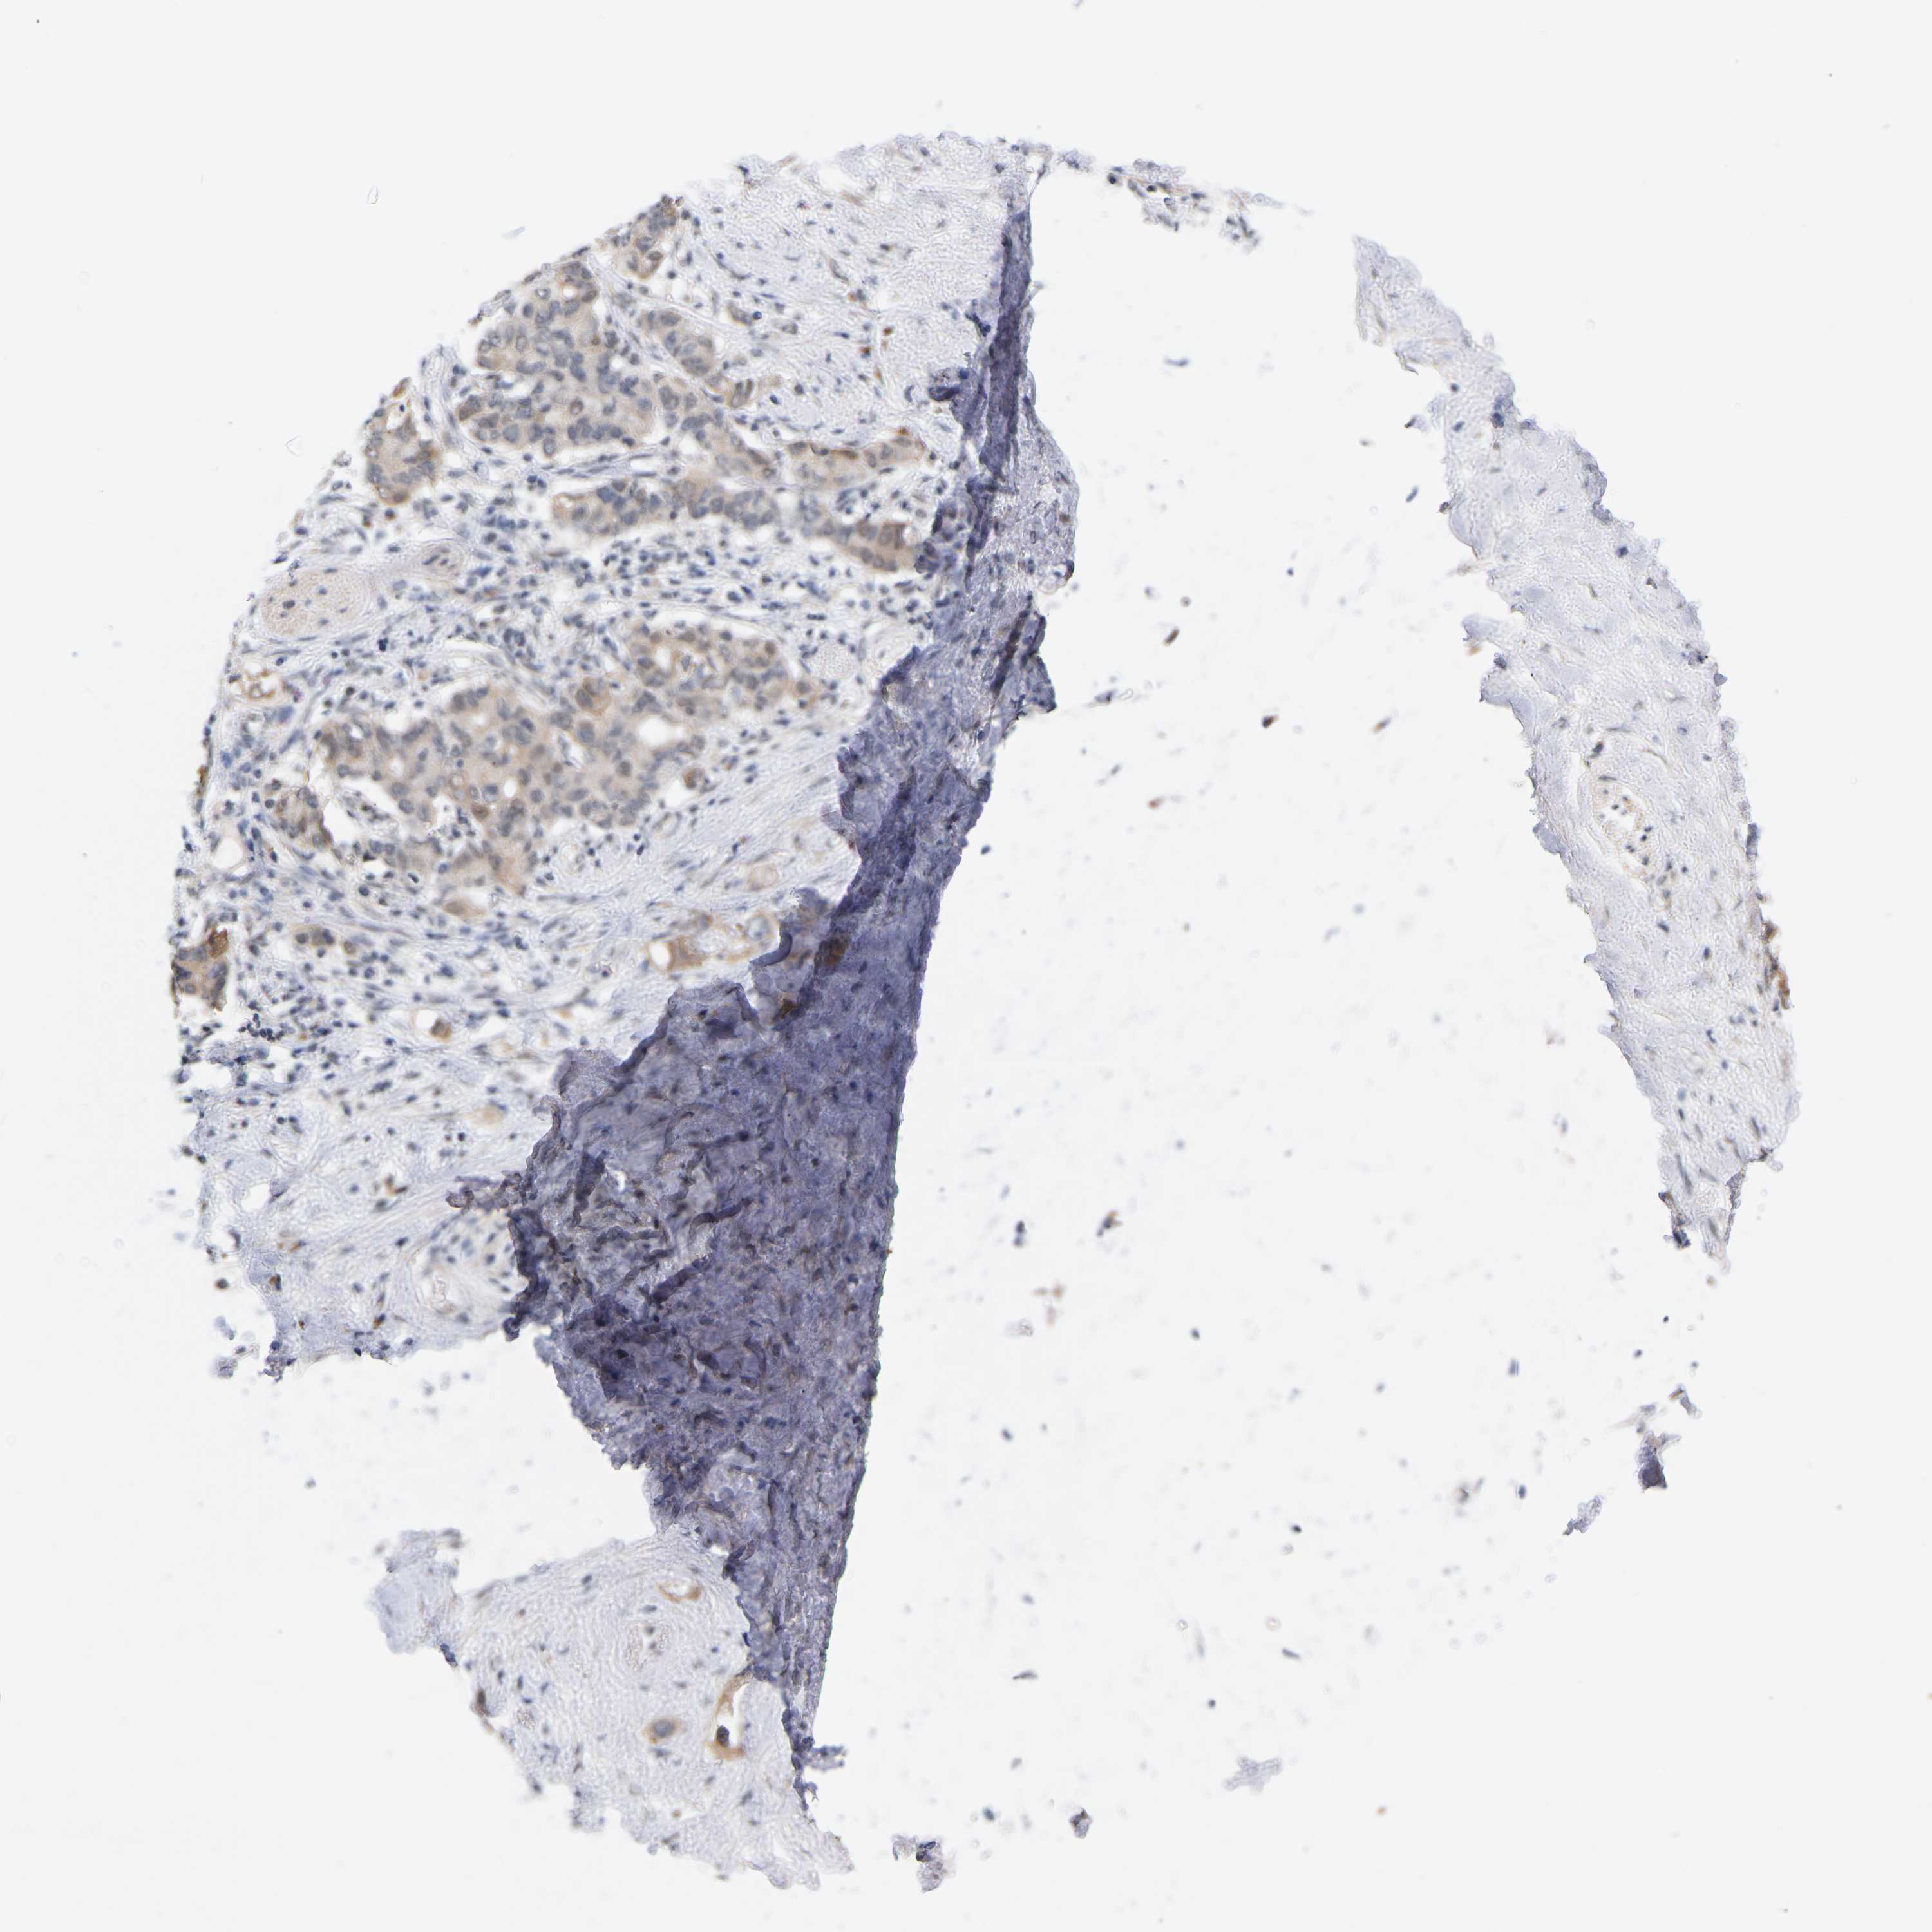

PANCREATIC CANCER - Protein expressioni

A mouse-over function shows sample information and annotation data. Click on an image to view it in a full screen mode. Samples can be filtered based on level of antibody staining by selecting one or several of the following categories: high, medium, low and not detected. The assay and annotation is described here.

Note that samples used for immunohistochemistry by the Human Protein Atlas do not correspond to samples in the TCGA dataset.

Antibody stainingi

Antibody staining in the annotated cell types in the current human tissue is reported as not detected, low, medium, or high, based on conventional immunohistochemistry profiling in selected tissues. This score is based on the combination of the staining intensity and fraction of stained cells.

Each image is clickable and will lead to virtual microscopy that enables deeper exploration of all samples and also displays staining intensity scores, fraction scores and subcellular localization as well as patient and tissue information for each sample.

Antibody HPA001818

Antibody CAB018352

Staining

High

Medium

Low

Not detected

Intensity

Strong

Moderate

Weak

Negative

Quantity

>75%

75%-25%

<25%

None

Location

Nuclear

Cytoplasmic/membranous

Cytoplasmic/membranous,nuclear

Adenocarcinoma, metastatic, NOS